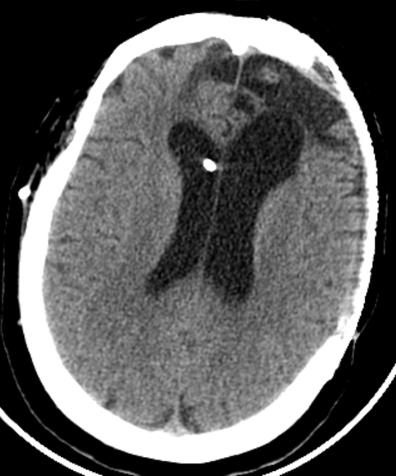

复阅2018年5月9日CT片:右枕顶部软组织肿胀、密度增高,右枕骨见线状骨质断裂、骨折线累及斜坡,右枕部颅板下见梭形致密阴影,大脑镰旁见线状致密阴影,左额颞部颅板下见弧形致密阴影,右额叶及左额颞叶均见斑片状高低混杂密度影,尤以左额叶明显,右侧小脑见斑片状高低混杂密度影。提示右枕顶部头皮血肿,右枕骨骨折,右枕部硬膜外血肿,蛛网膜下腔出血,右颞部硬膜下血肿,右额叶及左侧额颞叶脑挫裂伤,右侧小脑挫裂伤。

图1-5,2018年5月9日 CT片,右枕顶部头皮血肿,右枕骨骨折,右枕部硬膜外血肿,蛛网膜下腔出血,右颞部硬膜下血肿,右额叶及左侧额颞叶脑挫裂伤,右侧小脑挫裂伤